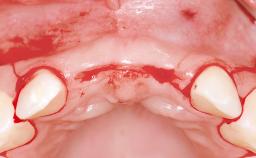

Replacement of Four Incisors with a Fixed Partial Denture on Two Narrow-Neck Implants after Implant Failure

| Bone Augmentation | Horizontal|Staged|Vertical |

| Augmentation Materials | Autogenous block(s)|Xenogenous|Membrane |